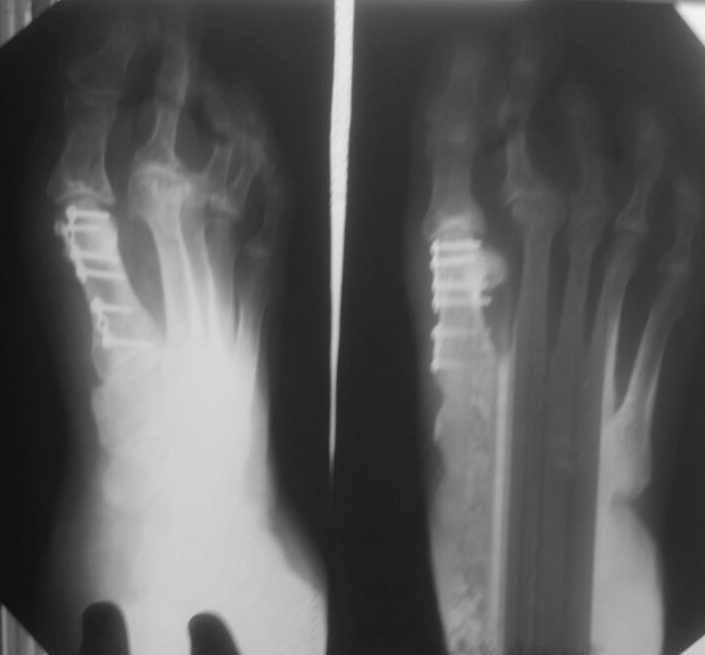

женщина средних лет, оперирована около года назад

Насколько я понял, беспокоит метатарсалгия. Достаточно будет укоротить

II-IV? Что-то другое? на что обратить внимание?